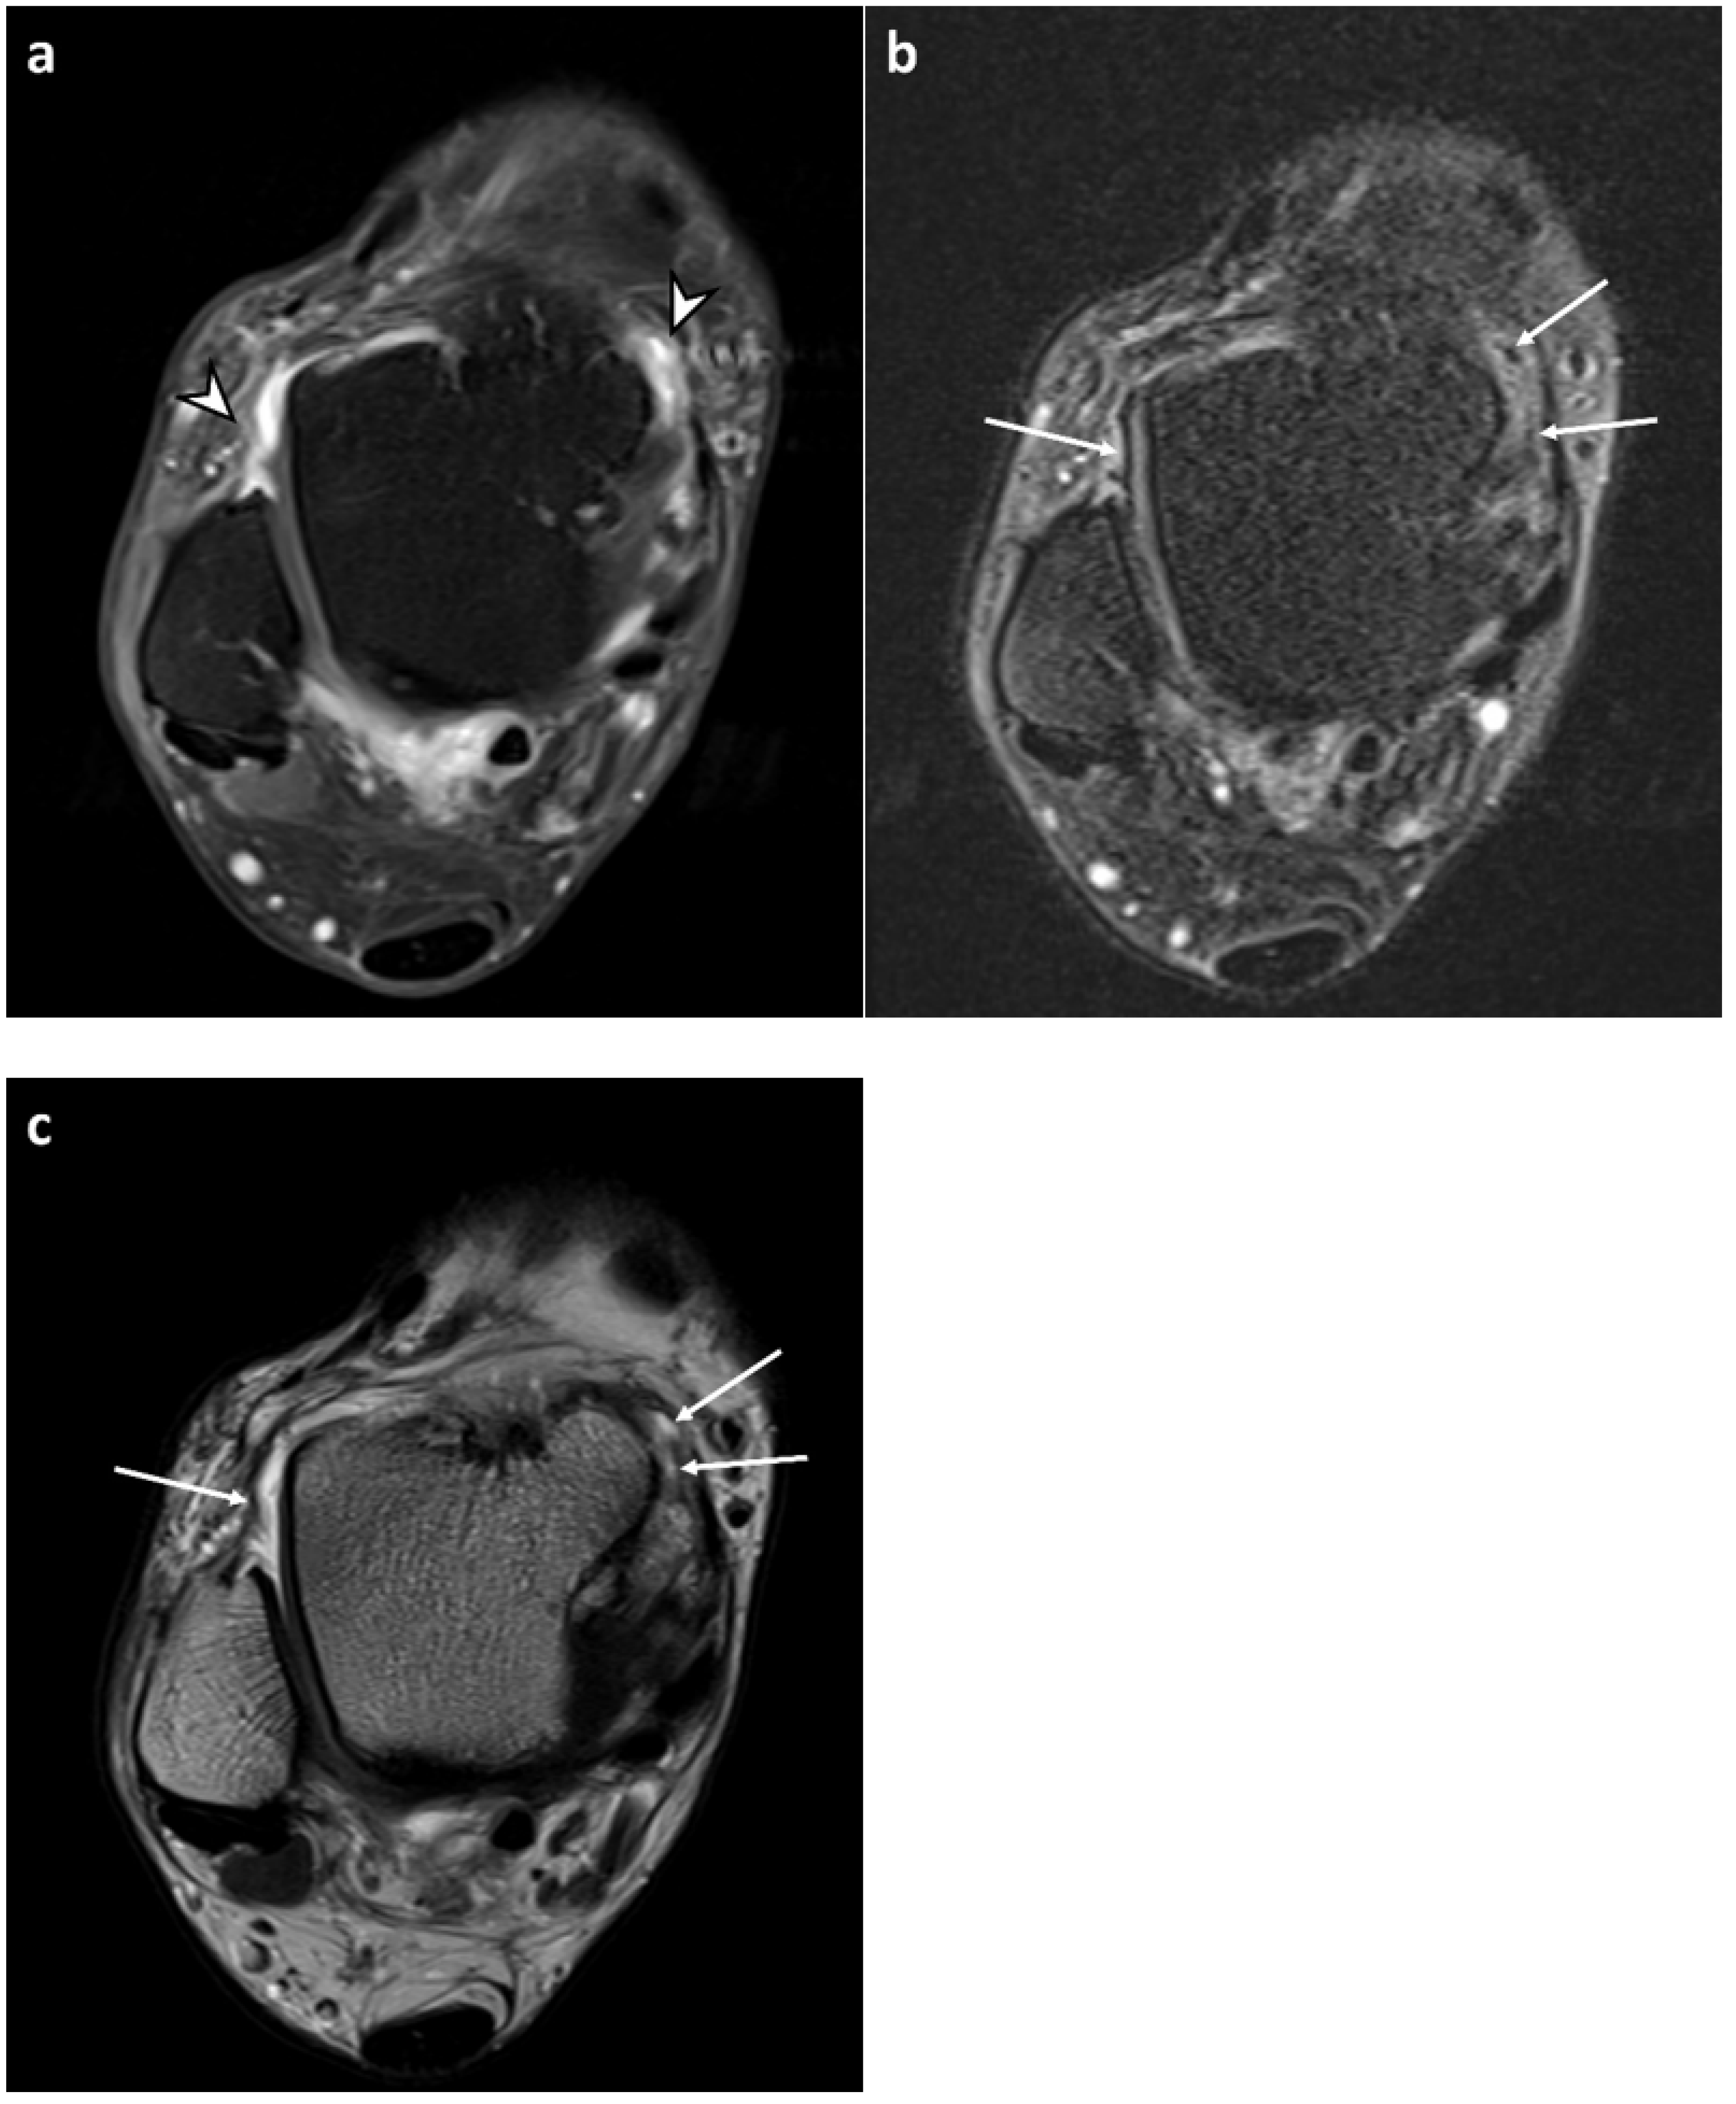

3.2. Synovial Visibility on FLAIR-FS and CE-T1 Images